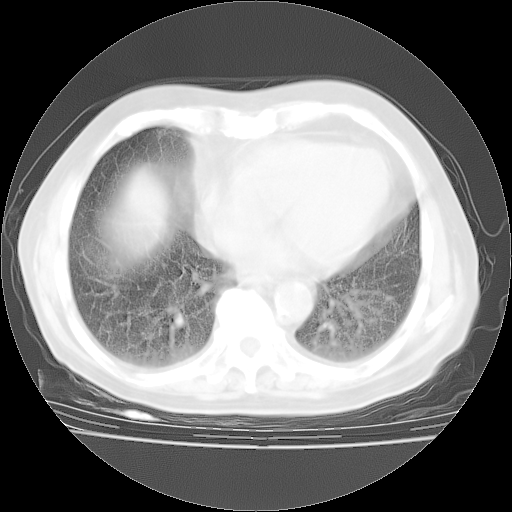

4月28日肺部CT——再次出现类似去年5月9日——透光度降低,“间质性”改变。

4月28日肺部CT——再次出现类似去年5月9日——磨玻璃样、间有“粟粒样”改变。